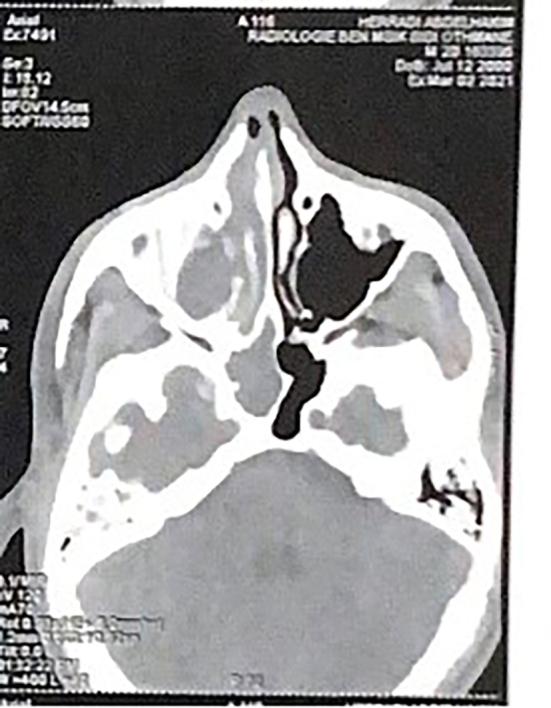

与上颌窦后鼻孔息肉复发相关的预后因素评估:病例系列及文献综述

Evaluation of prognostic factors associated with antrochoanal polyp recurrence: Case series and literature review.

Despite being non-neoplastic and usually unilateral, antro-choanal polyps have a notable tendency to recur following surgical treatment, particularly when incomplete removal of the polyp's antral portion occurs. Understanding the mechanisms and risk factors associated with ACP recurrence is crucial for optimizing treatment strategies and minimizing the likelihood of relapse. The main objective of this study was to identify and analyze the prognostic factors associated with recurrence of this benign but potentially recurrent pathology.

METHODS

This is a retrospective study of a series of 27 patients operated for an antrochoanal polyp (ACP). The study was carried out over a five-year period, from January 2, 2017 to July 5, 2024. All patients, regardless of age or sex, who underwent surgery for an antrochoanal polyp during this period were included in the study.

RESULTS

A total of 21 patients had no recurrence during follow-up. Of these, 14 patients (67 %) underwent endoscopic nasal endoscopy with meatotomy. However, 7 patients (33 %) underwent Caldwell-Luc (CWL) approach associated with endoscopic surgery. Recurrence was noted in 6 patients (22.22 %). The mean time to recurrence was 22 months, of which 4 (66 %) recurred before 16 months. We found that 50 % of patients who recurred (3 cases) were aged between 13 and 36, 17 % were under 13 (1 case) and 33 % were over 36 (2 cases). Recurrences were equally distributed between the genders, with a sex ratio of 1. All patients who had recurrence were of urban origin. Three patients, i.e., 50 % of those who recurred, had a rhino-sinus history. All patients who had relapsed underwent exclusive endonasal endoscopy with middle meatotomy for removal of the sinus component of ACP. Also, all patients had a tumor size greater than 5 cm. Following the results of our analytical study between the relapsed group (6patients) and the non-relapsed group (21patients), there were three prognostic factors found to be significantly associated with relapse with a p value <0.05. Associated endonasal pathology (p = 0.040) increases risk of recurrence. Tumor size ≥5 cm (p = 0.005). Incomplete surgical excision (p = 0.020).

CONCLUSION

Relapse of antrochoanal polyps is often due to incomplete surgical removal and persistent inflammation. Proper identification of recurrence risk factors and the use of complete endoscopic excision with wide maxillary antrostomy are essential to reduce recurrence. Long-term follow-up is crucial for early detection and effective management.